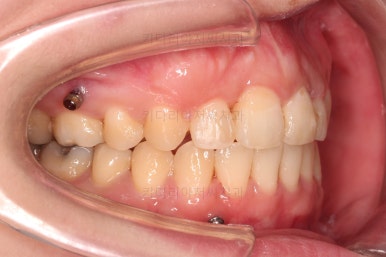

어금니쪽을 자세히 관찰해 보면, 위아래 어금니의 맞물림(교합)이 어긋나 있는데요.

톱니바퀴처럼 물려야 되는 교합이 한 칸 씩 윗니가 아랫니보다 앞으로 나가있는 앵글씨 2급 부정교합 상태였습니다.

미니스크류를 적절히 사용해서 부정교합도 맞추고 입매도 약간 들어가게 혹은 너무 들어가지 않게 조절해 주고요.

치열의 경사 등등도 조절해 줍니다.

부산부정교합이긴 하지만 애초에 입매가 많이 나쁘진 않았기 때문에 자칫하면 입이 너무 들어갈 수 있어 중간중간 환자분과 상의하여 너무 들어가지 않게끔 조절해 줍니다.

윗니만 발치를 했지만 교합이 잘 맞고요.

한 쪽 송곳니가 없지만 기능적으로 전혀 문제를 못느끼실 교합을 맞춰놨고요.